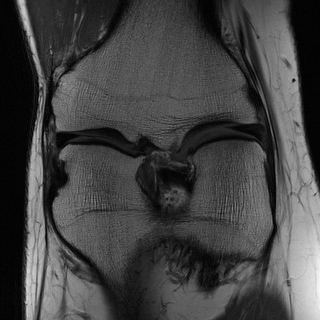

Edge preserving has always been a crucial concern in the design of reconstruction models. To improve the quality of reconstructed images and preserve image edges, some works suggested introducing edge priors in the original restoration problem to preserve image edges [4, 34]. However, they will suffer from complicated algorithm design and time-consuming training processes. Recently, some more efficient methods have been proposed to use edge maps as external guidance for image restoration. For example, Yang et al. [48] used off-the-shelf edge detectors to extract image edges from the degraded images. Fang et al. [12] predicted image edges by constructing an edge reconstruction network. Huang et al. [18] designed a novel dual discriminator GAN framework for solving fast multi-channel MRI, in which one GAN network is built for edge information enhancement. Inspired by these methods, we also consider introducing image edge prior as external guidance to MRI reconstruction since 1) image edges are prominent and distinguishable features in MRI (see Fig. 1), which can serve as a good guide to the model to recover high-frequency details; 2) the ground truth edges can be easily fetched via ordinary edge extraction operators, like Canny, Sobel, and Prewitt, which means that the edge maps can be learned in a data-driven manner. However, how to effectively utilize image edge priors to guide image reconstruction still remains a challenge. In some methods, edge information was simply concatenated with the input image and passed to the next stages. Though this is a simple way to utilize the edge priors, it may not give full play to the guiding role of the edge priors. Therefore, in this work, we want to explore a more efficient and effective mechanism to fully take advantage of image edge priors.

(a)

(b)

(c)

fastMRI is a large-scale MR dataset jointly established by Facebook AI Research and NYU Langone Health. It provides both knee and brain datasets for evaluation. In our work, we use the multi-coil knee dataset, which was acquired on three clinical 3T systems or one clinical 1.5T system using a 15-channel knee coil array. The dataset includes data from two pulse sequences, yielding coronal proton-density weighting with (PDFS) and without (PD) fat suppression. As is shown in Fig. 1, PD images usually contain more structural and prominent edge features than PDFS images, which suggests that it is more challenging to use edge guidance on PDFS datasets. Therefore, we explore the effectiveness of EAMRI on these two modalities. Following [13], for both PD and PDFS knee datasets, we separately filter out 227 volumes (8332 slices) for training and 24 volumes (1665 slices) for testing. The dataset is centrally cropped to .